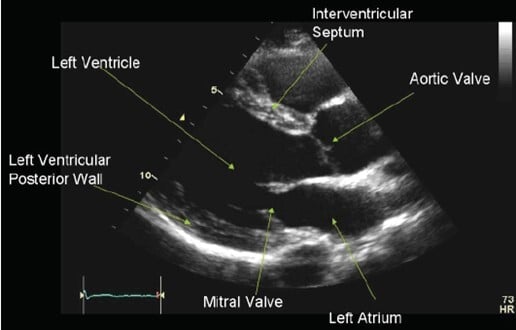

En la práctica cardiológica, la evaluación de la función sistólica del ventrículo izquierdo se ha basado históricamente en la fracción de eyección (FEVI), un parámetro ampliamente validado que refleja la capacidad de bombeo del corazón. Sin embargo, su principal limitación radica en que suele evidenciar alteraciones en etapas más avanzadas del daño miocárdico.

La fracción de eyección representa el porcentaje de sangre expulsada por el ventrículo izquierdo en cada latido en relación con el volumen al final de la diástole. Es el indicador más utilizado en cardiología clínica, con valores normales que oscilan entre 52–72% en hombres y 54–74% en mujeres.

El strain del ventrículo izquierdo surge como una herramienta complementaria que permite evaluar la deformación del miocardio durante el ciclo cardíaco. Mediante técnicas de ecocardiografía con speckle tracking, es posible analizar el comportamiento de las fibras miocárdicas con mayor sensibilidad, detectando alteraciones funcionales antes de que se manifiesten cambios en la FEVI.